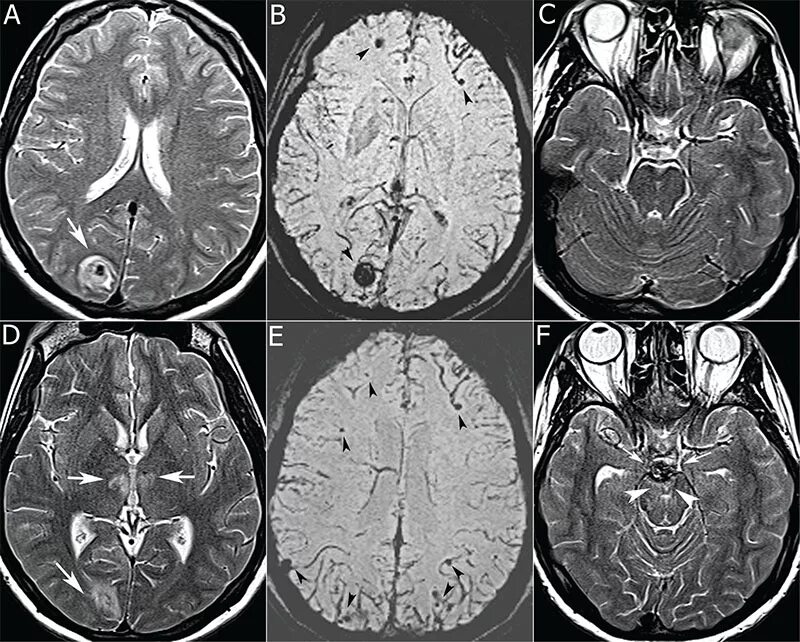

Томограмма глаза